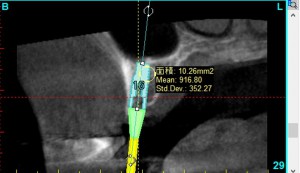

その際、クリニックでは、院内で撮影したCTをインプラント治療シュミレーションソフトで分析し、下記のような評価法と対比させ、骨の状態を判断に用いています。

骨の評価を5段階に分類し、その情報をもとに、手術方法を微妙に変化させます。

たとえば、このインプラントをいれる部分の骨は、mean 932となっているため、D2の十分な骨の硬さがあるため、安定したインプラントになりやすく、また、インプラントが安定するのに、短期間で済むことがわかり、インプラントの治療の期間が短くて済むと予測できます。

mean値を確認しながら、骨の状態を調べ、把握します。

最も骨の硬い部分を中心に安定しやすい場所にインプラントのシュミレーションをします。